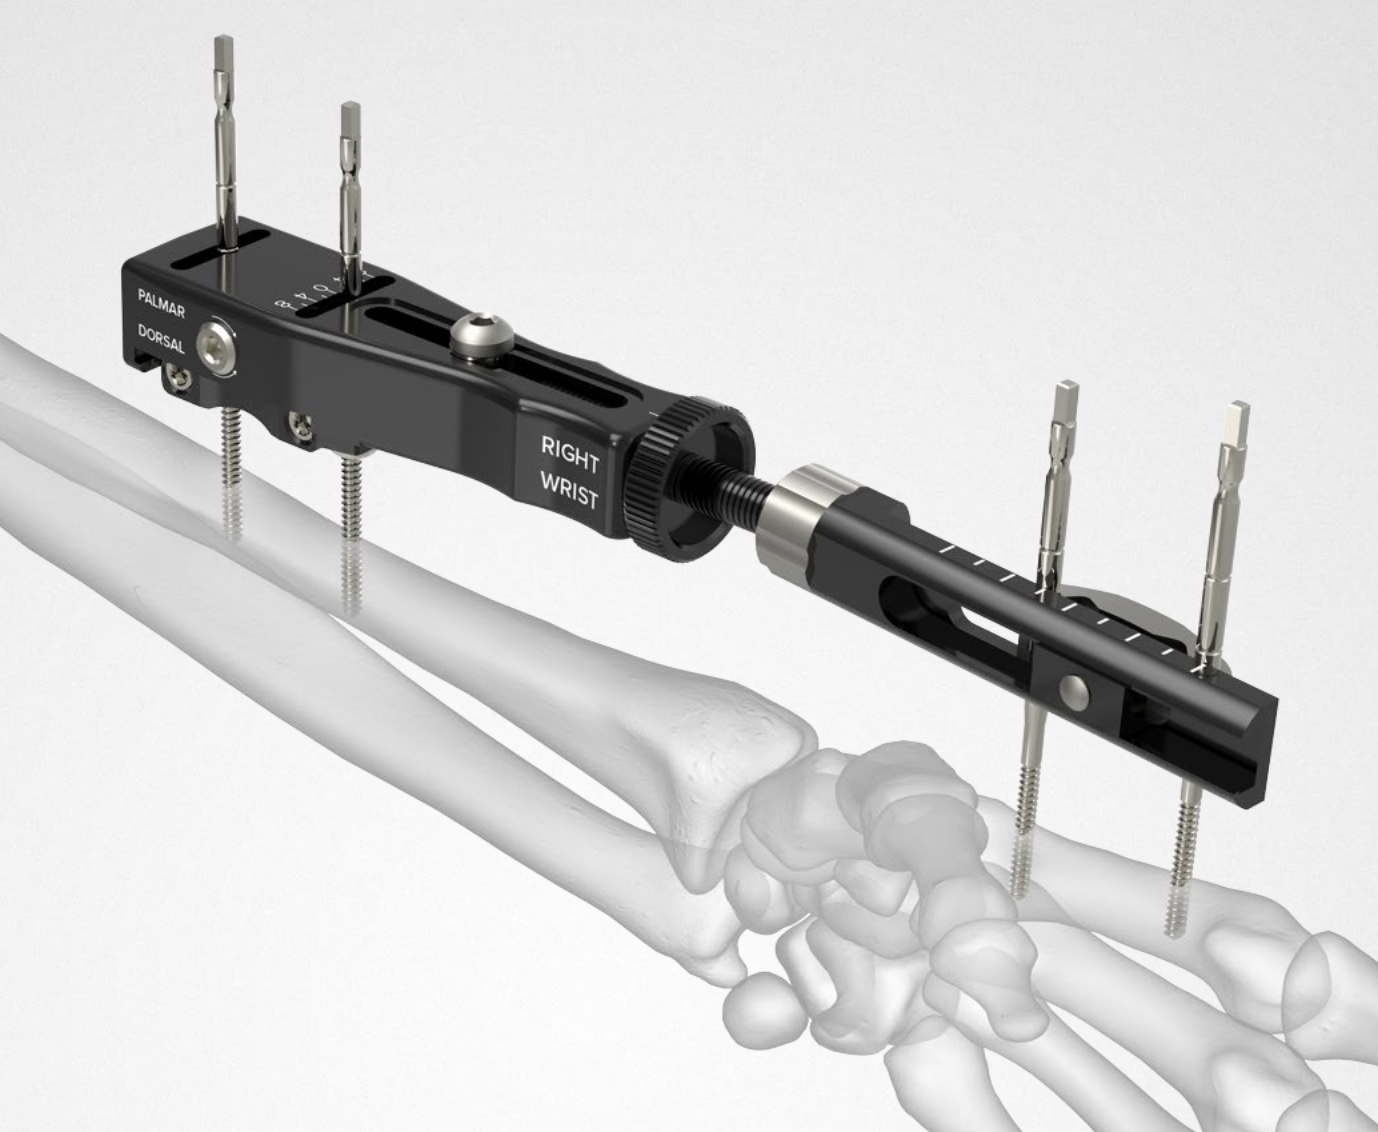

Dorsal distraction plating

Indication

Internal radiocarpal distraction

- unreconstructable distal radius fractures

- early weight bearing in poly trauma patients

- osteoporotic bone

Advantage - no pin site infection from external fixation

Disadvantage - need to remove plate at 3 - 4 months once fracture united

Technique

AO surgery foundation extended dorsal approach wrist

AO surgery foundation dorsal distraction plate

Arthrex dorsal spanning plate 2 incision video

Extended dorsal approach

- protect sensory radial nerve

- open 3rd extensor compartment / retract EPL radially

- mobilized 4th extensor compartment / retract EDC ulnarly

- bare area of radius proximally between EDC and ECRB / ECRL

Fixation to 2nd or 3rd metacarpal first

- 2nd metacarpal: under 2nd extensor compartment

- 3rd metacarpal: under 4th extensor compartment

- reduce / distract joint

- +/- additional radius fixation

Results

- systematic review of dorsal distraction plating

- 50% of wrist flexion extension compared to contralateral limb

- grip strength 80%